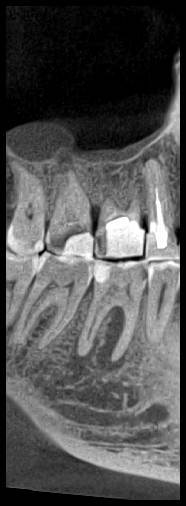

КТ от 04.03.2024

69273_3.jpg.f56a31dc1d8d53085767a9a52915128c.jpg69273_4.jpg.f9ec255bedbdb9fde8159318d3cb1fd9.jpg69273_5.jpg.36a7a942d403dd2eb062e5a4b2b58a52.jpg69273_6.jpg.492d3fbca3808fbdf58c86056b2fe0c3.jpg69273_7.jpg.f9bfdd5d593504dc7bd3710ece18aa4f.jpg69273_8.jpg.853e2342e6f2329a2e89c8939c2aad6f.jpg69273_11.jpg.e495813d50bf007f7165bf5f5dfec4b3.jpg69273_12.jpg.49b3cf66b4dd26b5cd68a91b2684e402.jpg69273_13.jpg.5d61b621b8e8b2c473ad6a8aca42502d.jpg